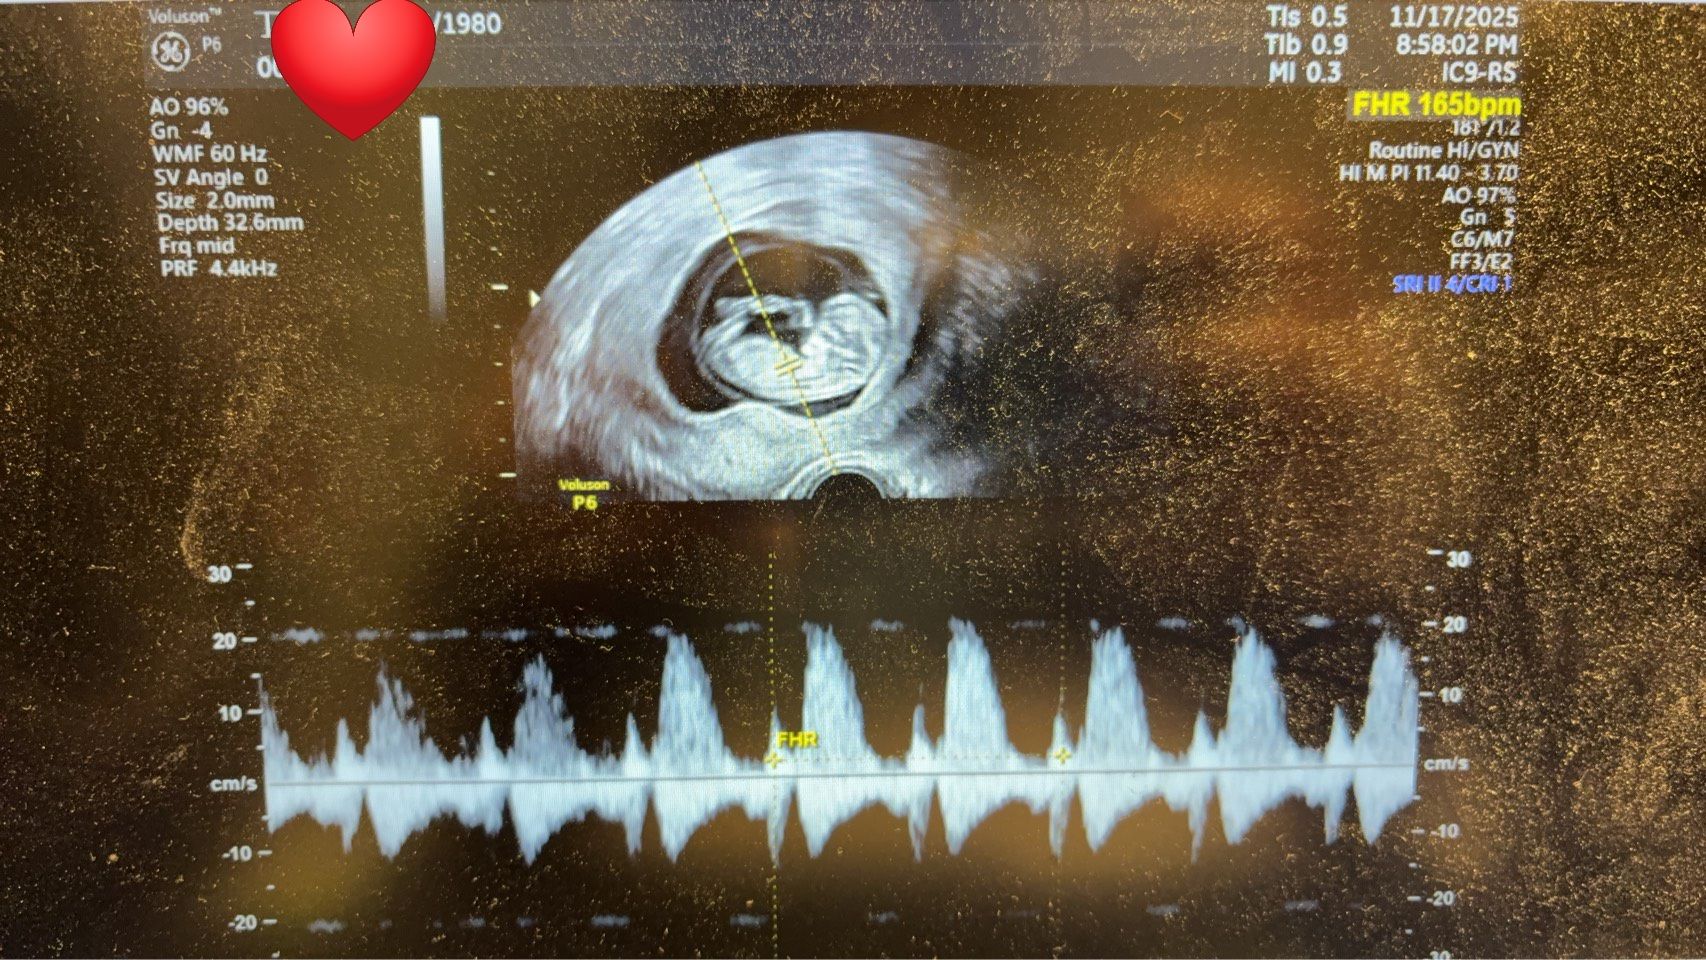

目前丁小姐已順利懷孕 11週並成功畢業,正式邁向幸福而期待的孕期旅程。